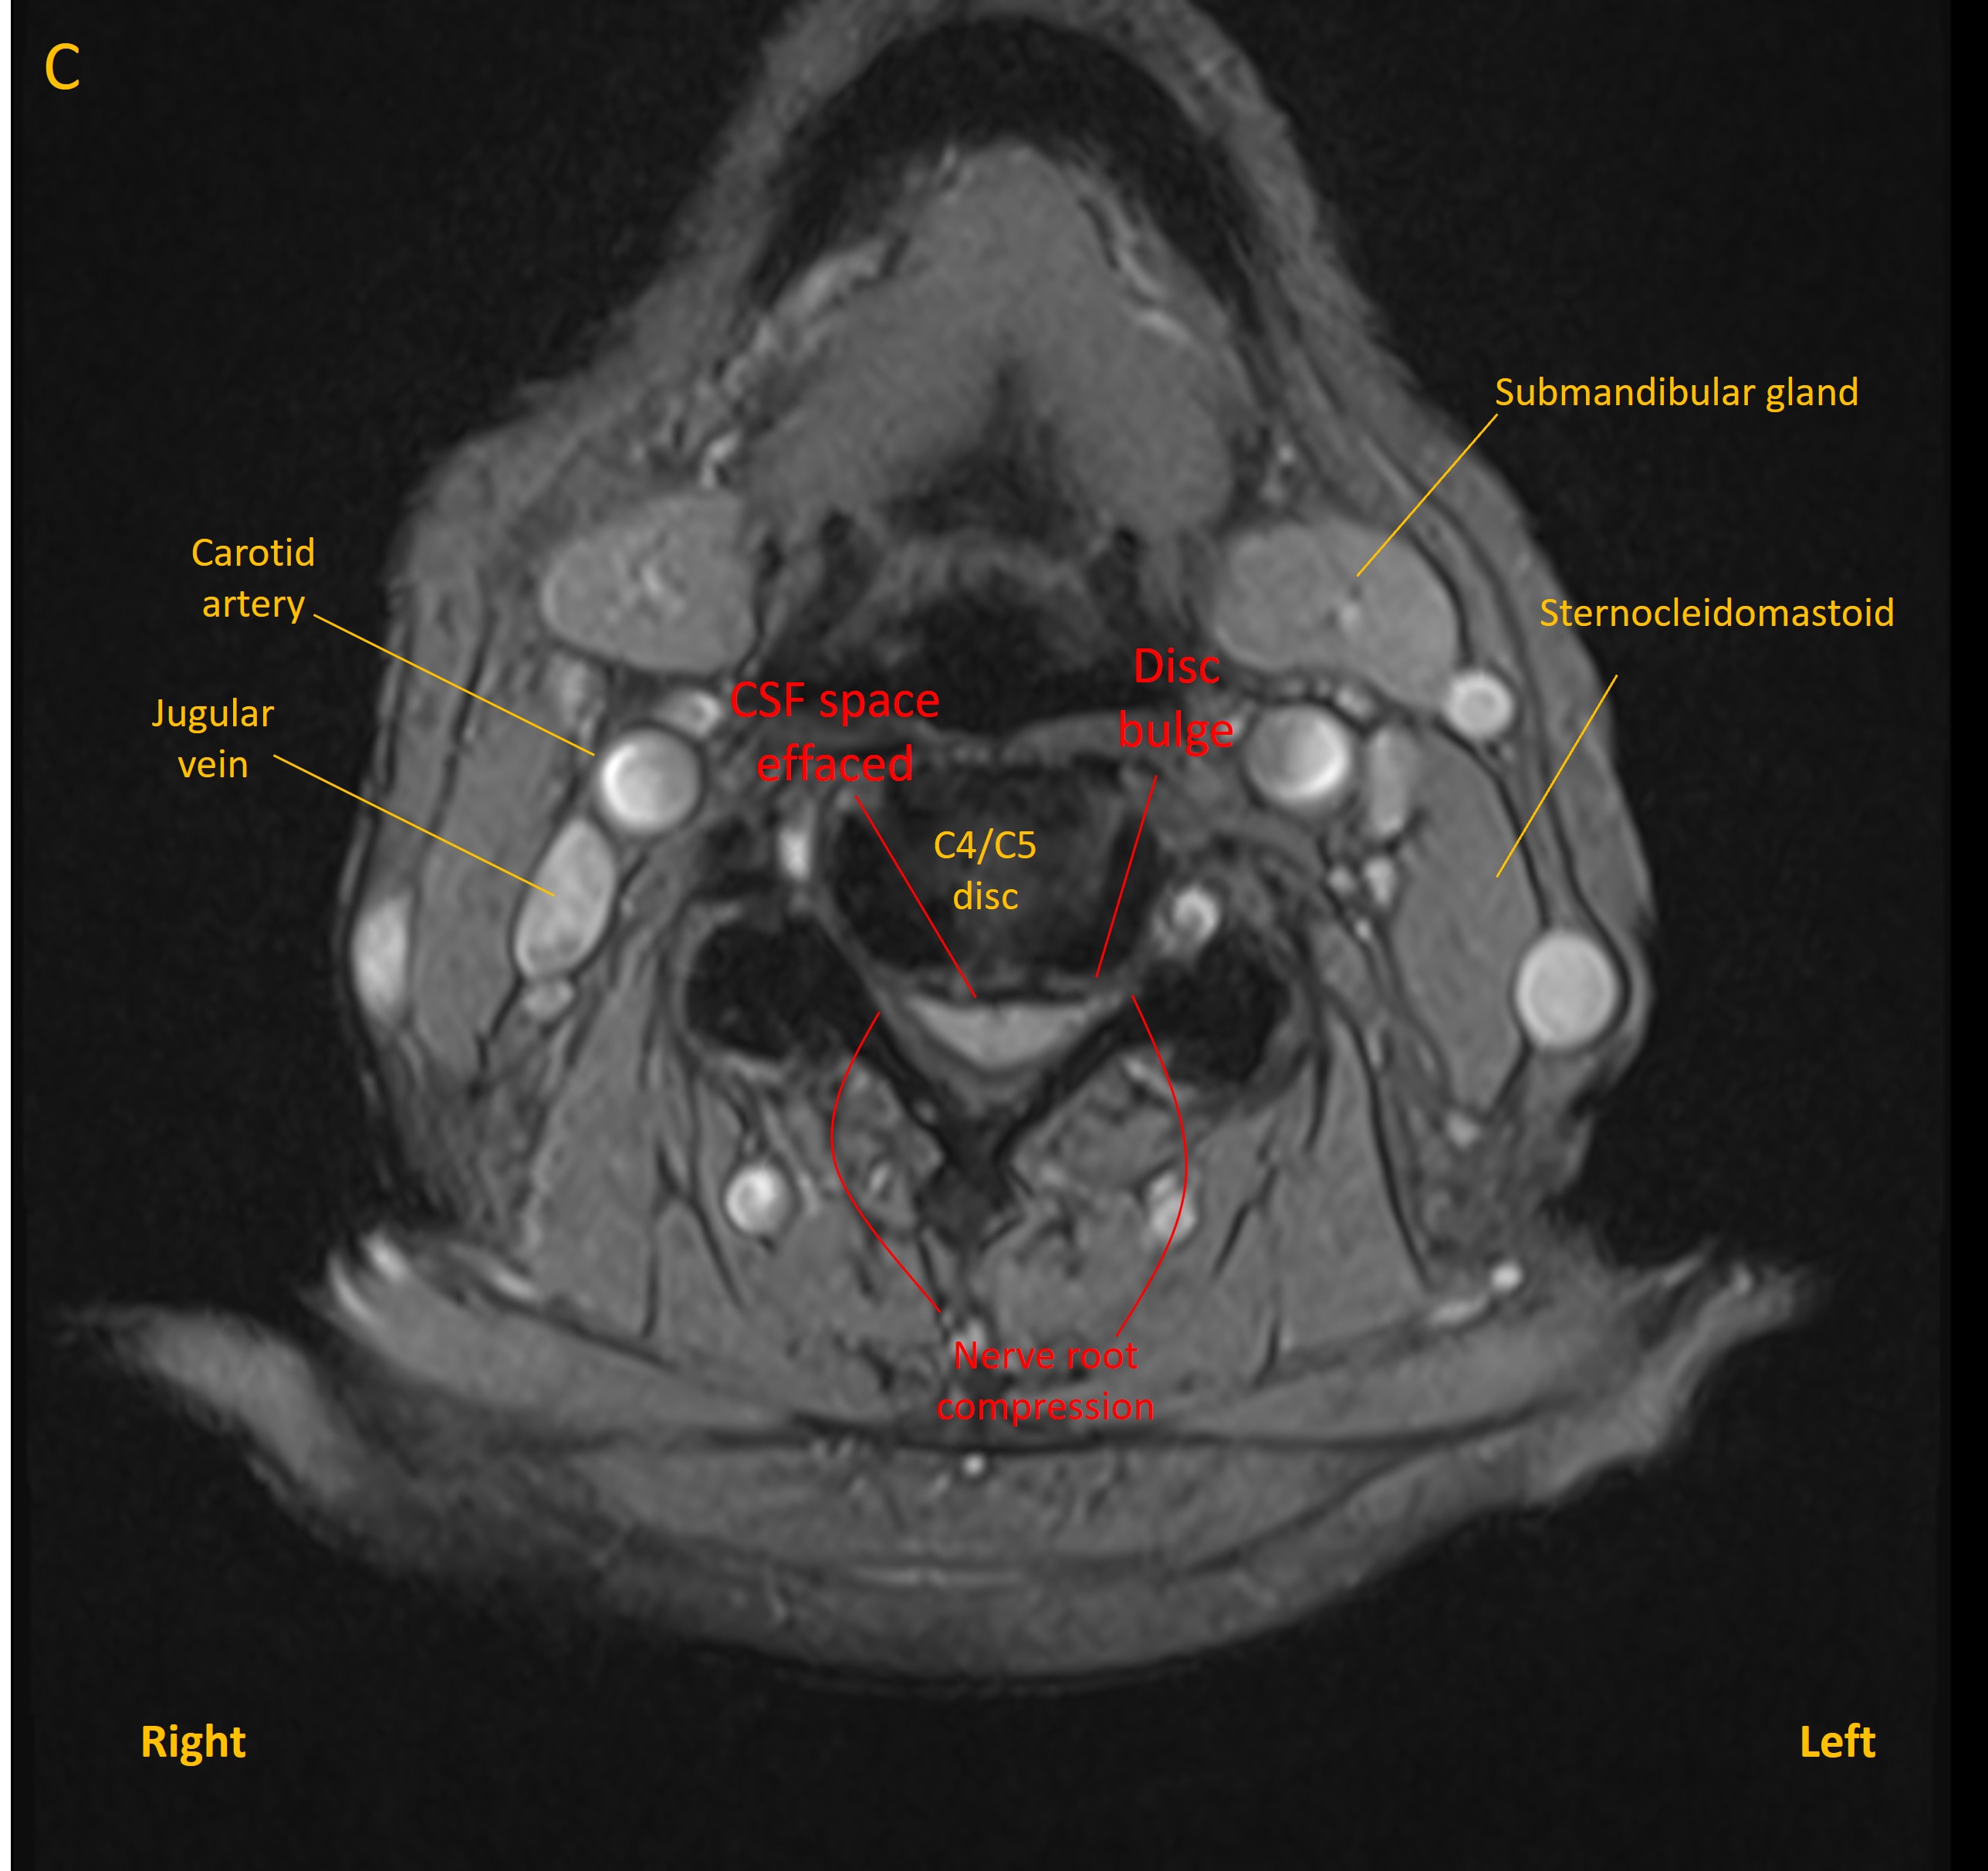

Degenerative changes were seen at multiple levels in the cervical spine, as is frequent at this age, and with some levels featuring mild narrowing of exit foramina and contact with nerve roots. These were evident at levels C3/C4 (B), C4/C5 (C) and C5/C6(D) - although none of these were clinically evident. Disc bulges at other levels did not compress the cord.

Axial MRI